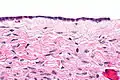

Serous cystadenomas are diagnosed by histomorphologic examination, by pathologists. Grossly, they are, usually, small unilocular cysts that contain clear, straw-coloured fluid. However, they may sometimes be multilocular. Microscopically, the cyst lining consists of a simple epithelium, whose cells may be either:[3]

- be columnar and tall and contain cilia, resembling normal tubal epithelium

- be cuboidal and have no cilia, resembling ovarian surface epithelium